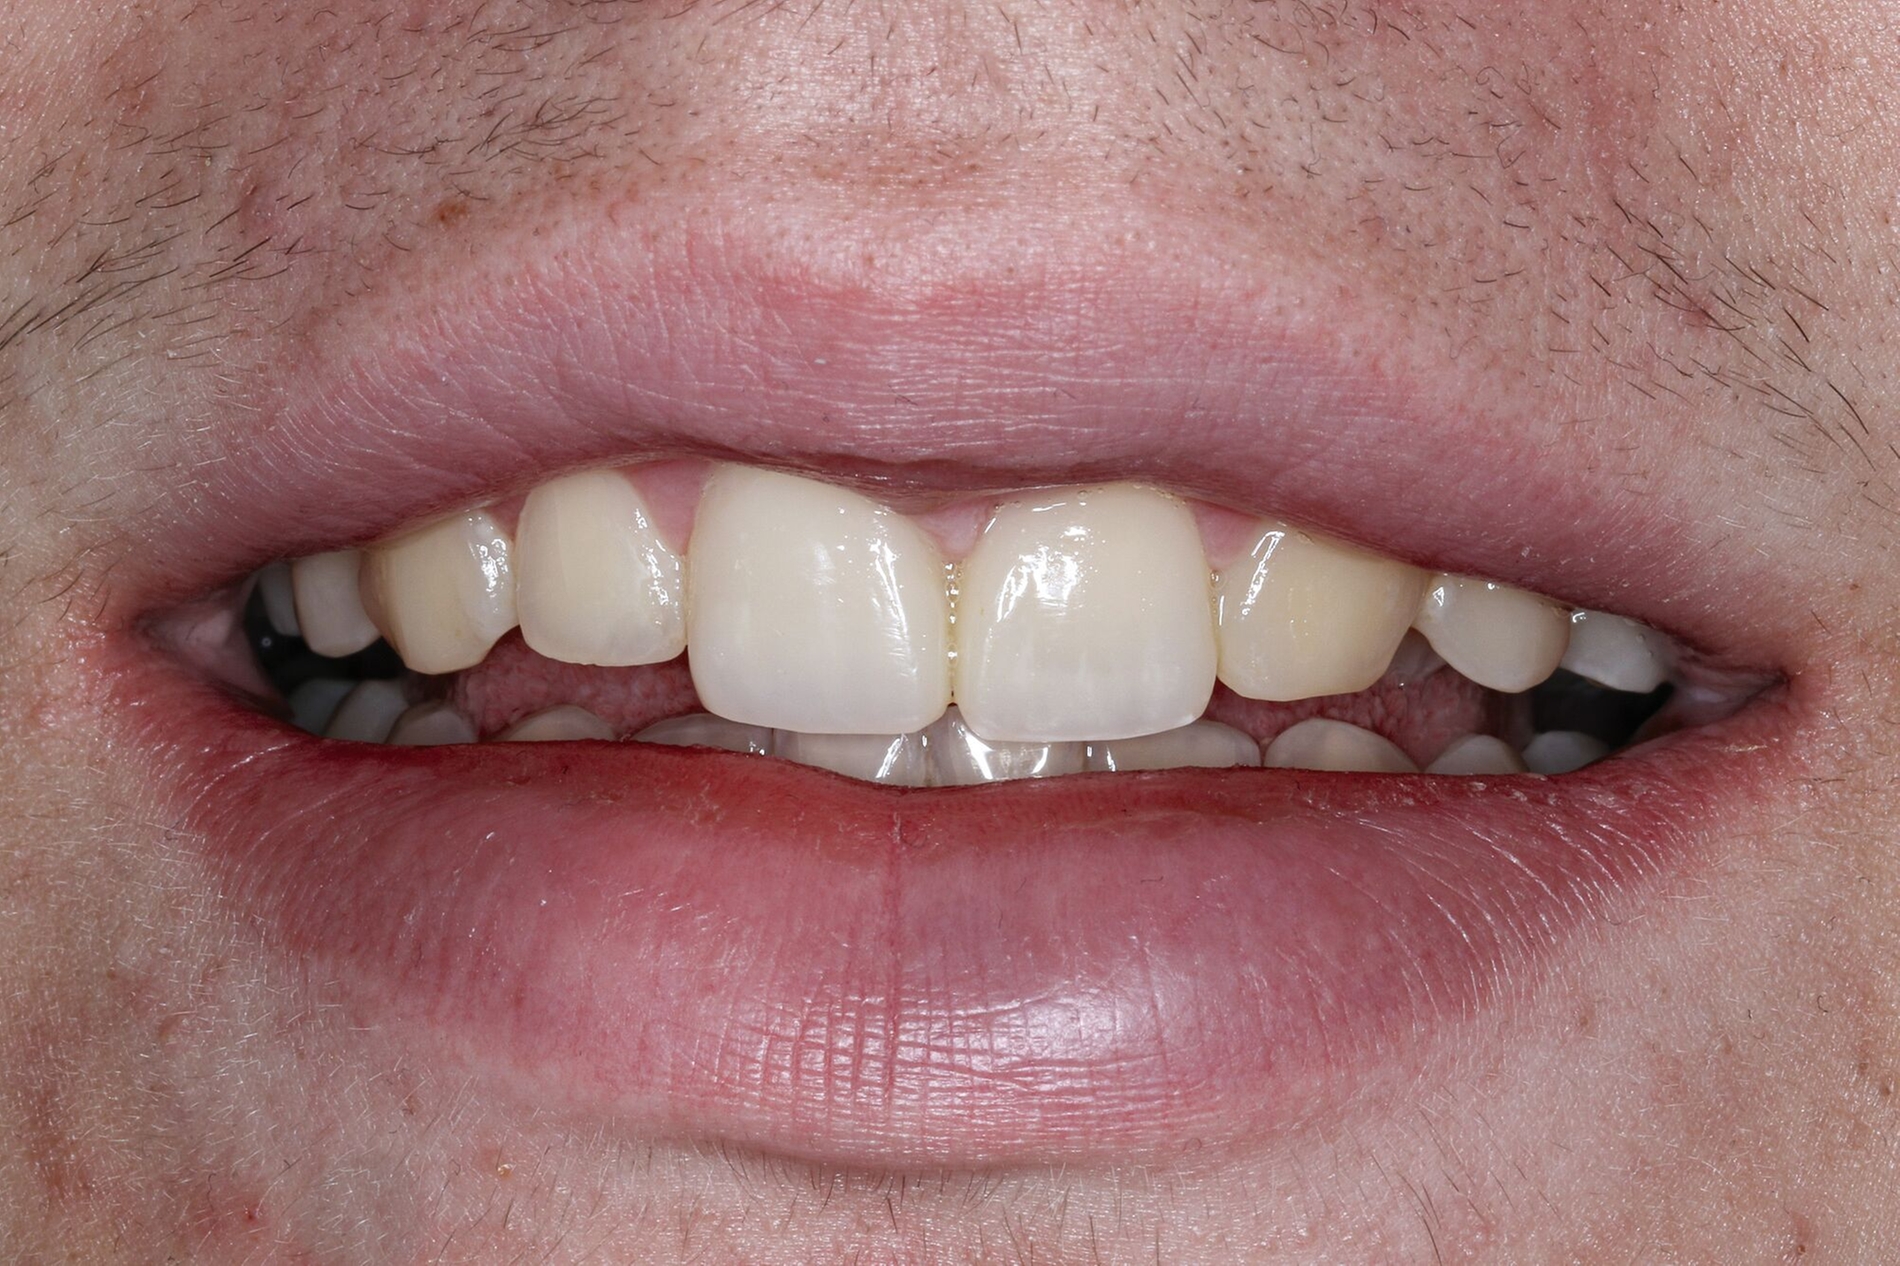

Wenn die Lückenversorgung durch eine Transplantation (siehe Teil 4 der Fortbildung „Dentales Trauma“: Chirurgische Aspekte) oder einen kieferorthopädischen Lückenschluss (siehe Teil 5 der Fortbildung „Dentales Trauma“: Kieferorthopädische Aspekte) vorbereitet wurde, beschränkt sich die restaurative Versorgung auf eine Formkorrektur der Zähne. Diese kann – je nach Situation und Präferenz des Behandlers – mit direkten (Abbildung 4) oder mit (minimalinvasiven) indirekten Restaurationen (Veneers, Teilkronen) erfolgen. Gerade bei jungen Patienten muss allerdings berücksichtigt werden, dass im Zuge der passiven Eruption [Mele et al., 2018] Veränderungen des Gingivaverlaufs an den restaurierten Zähnen zur Exposition der Restaurationsränder führen und eine neue Versorgung nach mehreren Jahren erforderlich machen können.